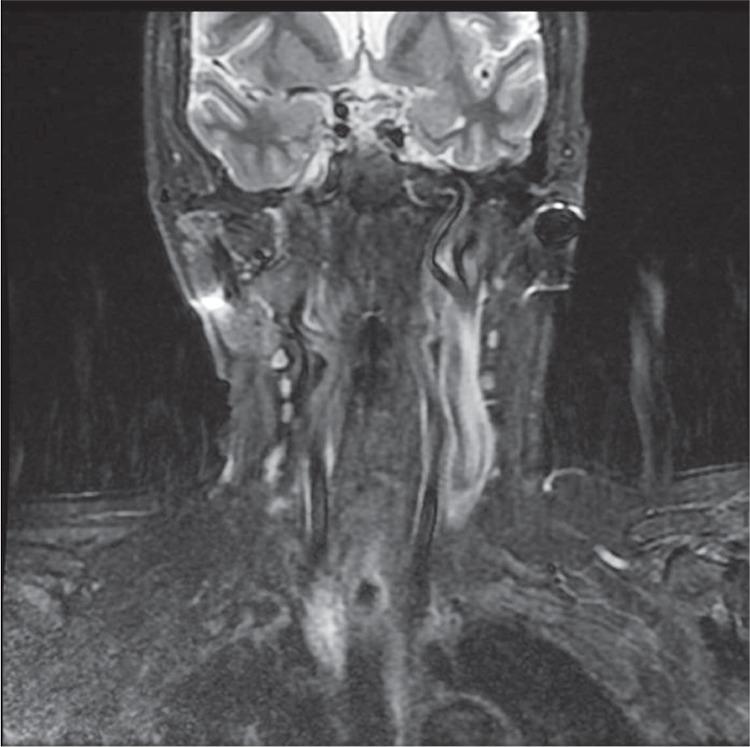

In this study we wanted to present a case with the history of multiple previous neck explorations and persisting upper mediastinal ectopic parathyroid adenoma who underwent a successful operation with radioguided minimal invasive approach.

在本研究中,我们想介绍一例有多次颈部探查病史且存在上纵隔异位甲状旁腺腺瘤的病例,该病例通过放射性引导下的微创方法成功接受了手术。